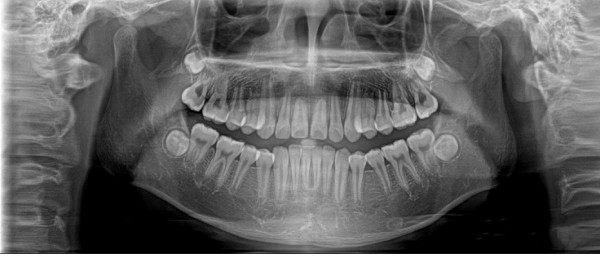

全景機(jī)基于體層攝影原理設(shè)計(jì)而成,全景攝影時,根據(jù)口腔頜面部的解剖特點(diǎn),X線球管圍繞人體頭部選擇約120°,從一側(cè)顳下頜關(guān)節(jié)到另一側(cè)顳下頜關(guān)節(jié),最后一次性獲得全口牙齒的2D圖像,使頜骨及全口牙體層攝影在一幅圖片上呈現(xiàn)左右展開的平面圖。

全景機(jī)具有觀察全面、操作簡便、兒童及老弱患者容易接受的優(yōu)點(diǎn)。然而,全景機(jī)的缺點(diǎn)也非常明顯:

1.相較牙片機(jī),全景成像中牙齒內(nèi)部的清晰度和細(xì)節(jié)明顯要略遜一籌;

2.由于是曲線體層成像,其圖像有比較嚴(yán)重的畸變失真,同樣也不可避免的具有影像重疊。

因此,全景機(jī)主要用于觀察所有牙齒的形態(tài)、位置及頜骨內(nèi)情況,為牙齒正畸矯正、牙齒修復(fù)提供圖像依據(jù),不太適合用于對牙齒結(jié)構(gòu)成像清晰度要求非常高的領(lǐng)域。